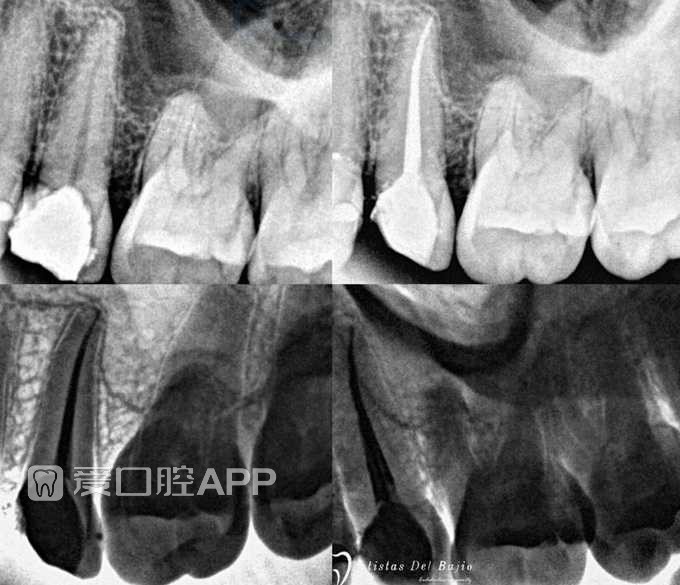

看个根充:上5 by Arcangel Cauich